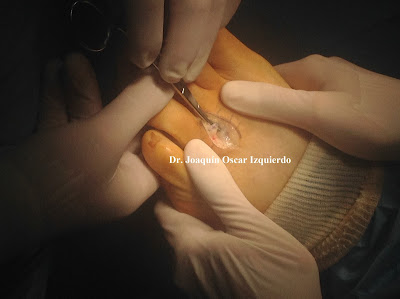

Hoy os pongo secuencia de una intervención de un neuroma de Morton.

(Test de Sullivan positivo) recordar que la mejor exploración clínica es realizar el test de Mulder y el de pinzamiento al mismo tiempo, de esta forma podemos estar seguros que estamos ante un neuroma de Morton. Posteriormente lo podemos comprobar con una ecografia.

(Test de Sullivan positivo) recordar que la mejor exploración clínica es realizar el test de Mulder y el de pinzamiento al mismo tiempo, de esta forma podemos estar seguros que estamos ante un neuroma de Morton. Posteriormente lo podemos comprobar con una ecografia.